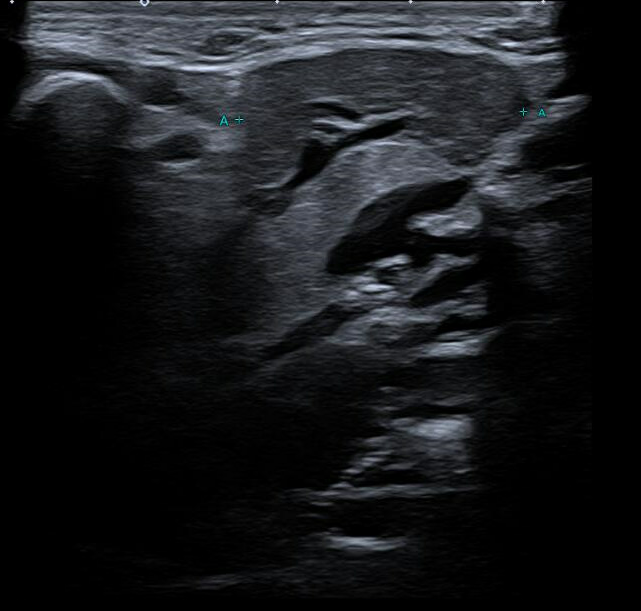

Exploración física: Tumoración dura, mal delimitada, de aproximadamente 2,5-3 cm de diámetro, adherida a planos profundos, no dolorosa. Sin signos inflamatorios cutáneos ni otras adenopatías palpables. Se realiza ecografía en consulta.

Hallazgos ecográficos

Ecografía clínica: masa hipoecogénica bien delimitada dependiente de la glándula submandibular derecha, sin evidencia de sialolitiasis. Dado el carácter inespecífico de la lesión, se deriva al servicio de Otorrinolaringología (ORL) para estudio.

Valorado por ORL, faringoscopia normal y solicitan ecografía cervical reglada, confirmándose alteración hipoecogénica de 8,6 × 27 × 21 mm en la porción superficial de la glándula submandibular derecha, globulosa, heterogénea, con bordes definidos y sin adenopatías asociadas. Dilatación ductal asociada. Se realiza PAAF ecoguiada, planteando dudas diagnósticas entre cambios inflamatorios crónicos o proceso infiltrativo.